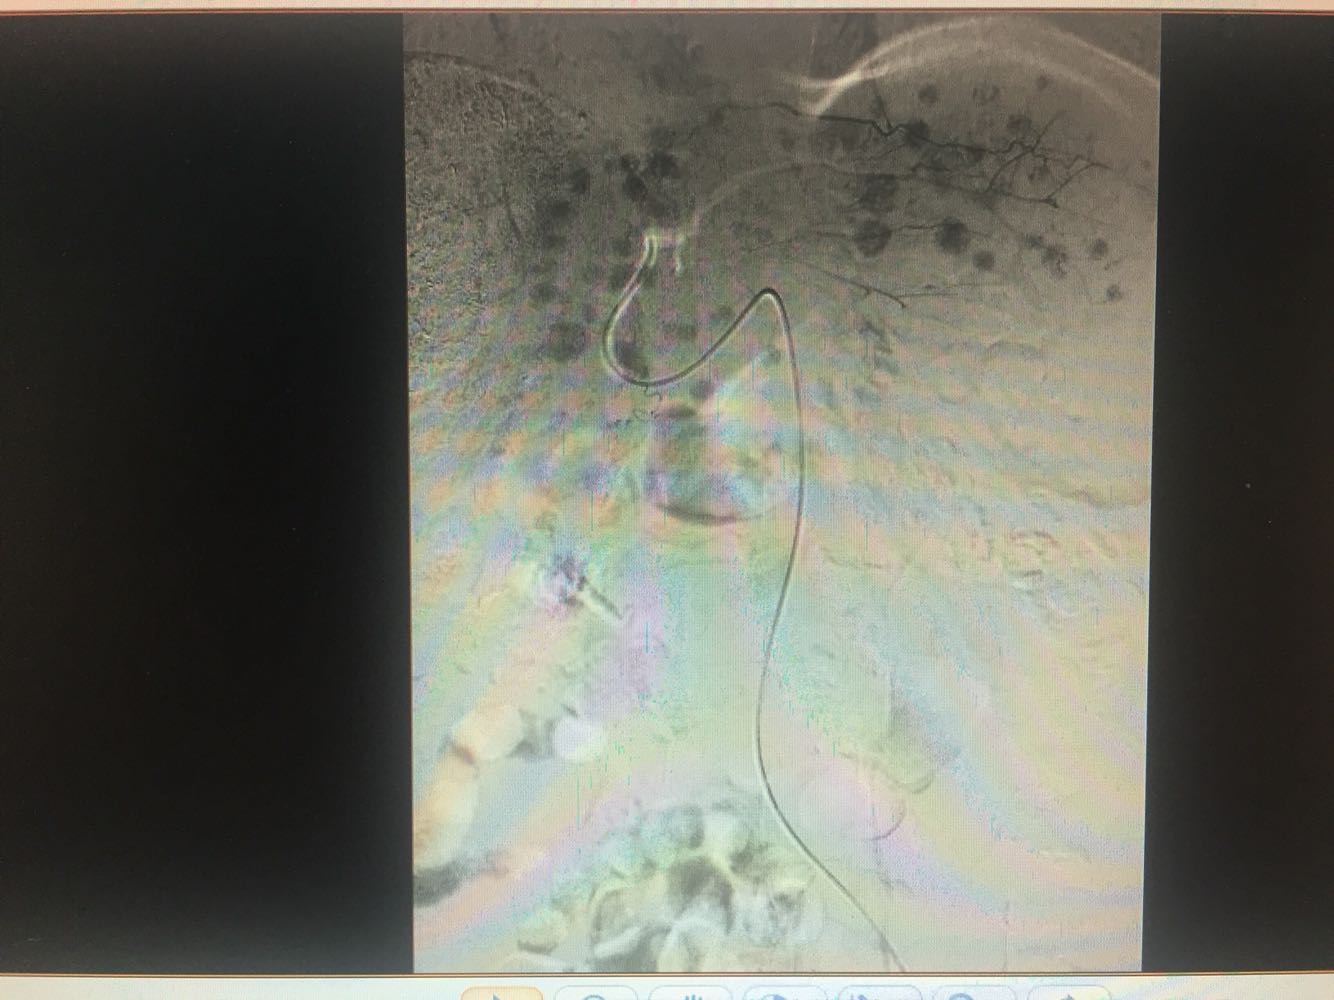

乙肝肝硬化,原发性肝癌,保肝抗病毒治疗,及TACE

出院一月后复查,行增强CT扫描,肿瘤明显缩小,肝功能正常,乙肝病毒复制转阴,建议继续口服恩替卡韦抗病毒治疗